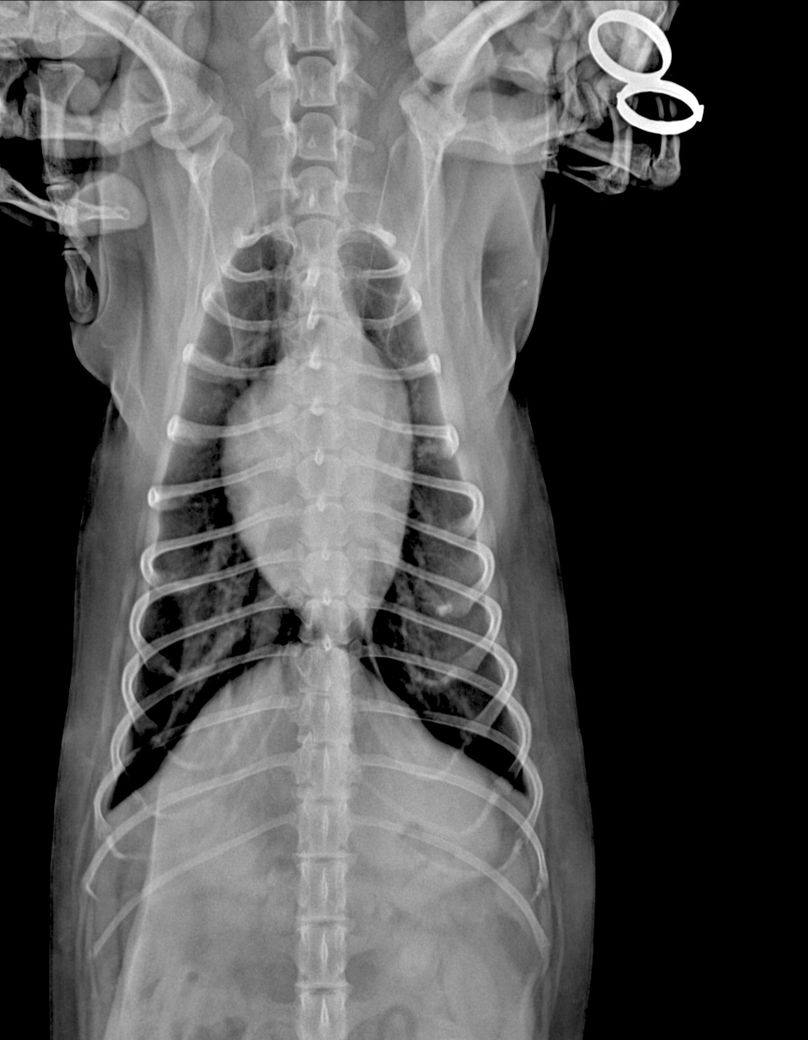

안녕하세요 강아지 건강검진 받고 엑스레이상 흉골이 휘었다고 했었는데요, 외부충격은 없고, 1년 전 다른 병원에서 찍은 엑스레이는 흉골 휘지 않았습니다. 사진상으로 휘어보이는거라고 하셨는데 잘못찍혔다는 말씀이실까요?

건강검진 병원에서는 1년전 다른 병원에서 찍은 엑스레이는 흉골이 휘지 않아서 폐쪽 문제일수도 있으니 ct가능한 병원가서 정확하게 보는게 좋을거같다는데, 폐에 문제가 생기면 심장이 쏠리면서 흉골이 휠수도있나요..?

이전에 이미 몇차례 말씀 드린것처럼 촬영상의 rotation에 의해 일어난 artefact 즉, 허상에 해당하며 정상적인 현상입니다. 몇차례 반복해서 말씀 드린 내용이 믿음이 안가신다면 다른동물병원에 가셔서 가슴쪽 엑스레이를 다시 찍어 보시거나 주치의의 이야기 대로 CT 촬영을 해보시면 됩니다.